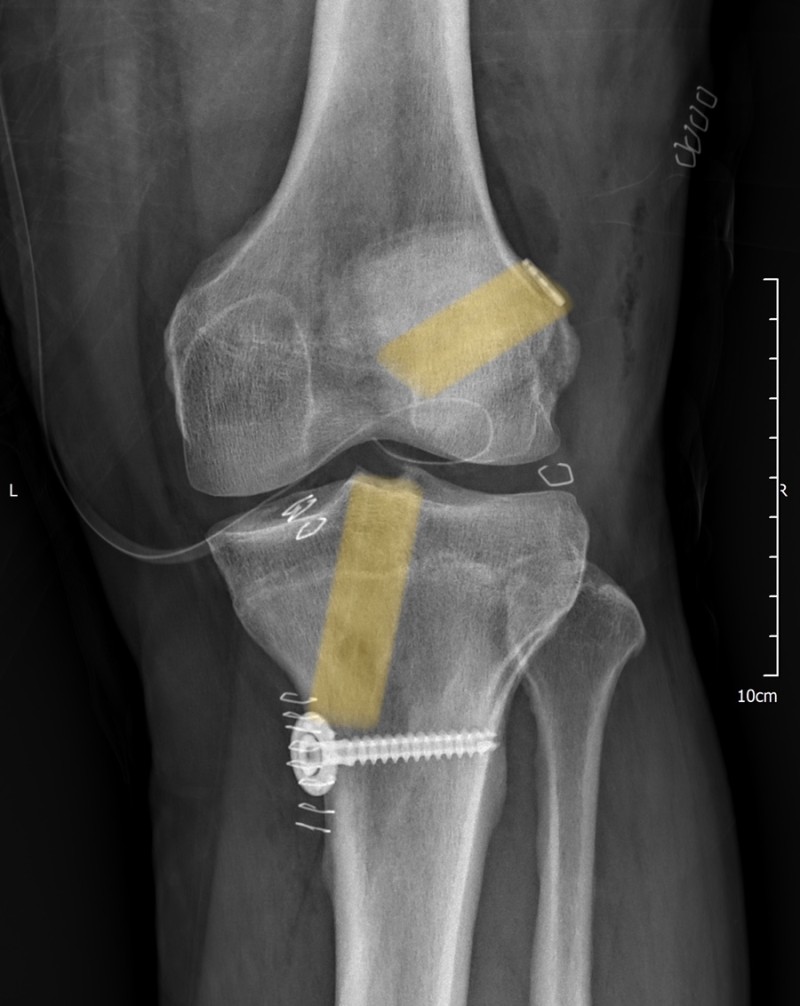

실제 본원 수술 사례

최근에 스키 및 축구 등으로 전방십자인대 파열되신 분이

여러분 오셔서, 지난주엔 두 건의 전방십자인대 재건술을

하였습니다.

Outside-in 술기를 통해 시행하였고,

1. 좌측 슬관절 전방십자인대 파열, 40대 남성

2. 좌측 슬관절 전방십자인대 파열, 30대 남성

두분 모두 XR 상에서 해부학적으로 좋은 위치에

터널이 형성되었음을 확인할 수 있습니다.